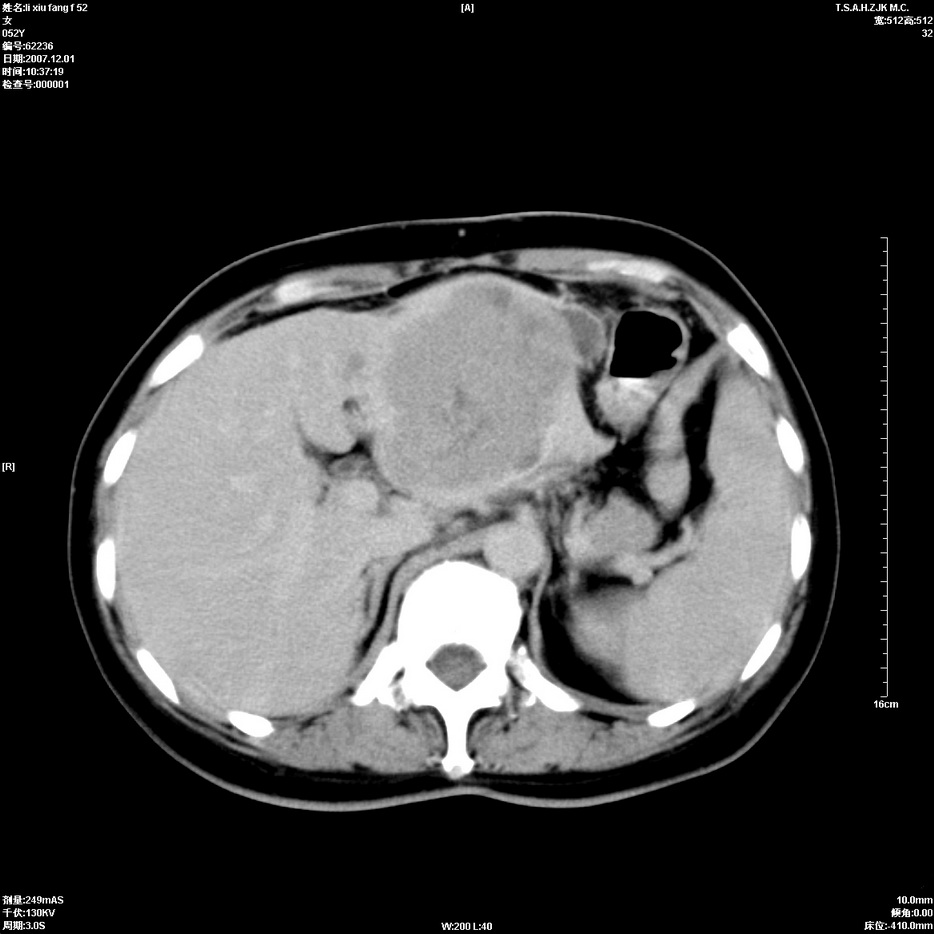

标题: CT12858:女,52岁,胎甲球蛋白861肝左叶占位,肝癌。下腔静 [打印本页]

标题: CT12858:女,52岁,胎甲球蛋白861肝左叶占位,肝癌。下腔静

肝左叶巨大低密度灶肿块,增强符合快进快出表现,有动静脉交通支;静脉期,下腔静脉内有充盈缺损,afp明显升高,支持肝癌并下腔静脉癌栓形成。

以下是引用拾荒者在2008-4-15 22:57:00的发言:[br]肝左叶巨大低密度灶肿块,增强符合快进快出表现,有动静脉交通支;静脉期,下腔静脉内有充盈缺损,afp明显升高,支持肝癌并下腔静脉癌栓形成。